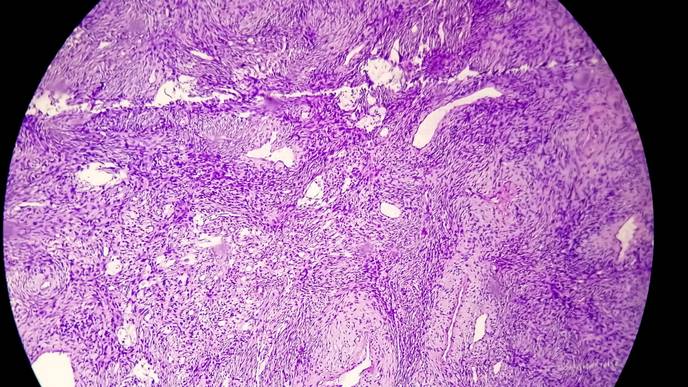

An acoustic neuroma, also referred to as a vestibular schwannoma, is a tumor that can grow on the nerve that connects the ear to the brain. Schwann cells wrap around nerve fibers to help support and insulate them, including hearing and balance nerves inside the ear. Overproduction of these cells, however, can cause tinnitus (ringing in the ear), hearing loss, dizziness, and loss of balance. If left untreated, the tumor can grow and place pressure on the nerve and nearby brain structures and become life threatening.